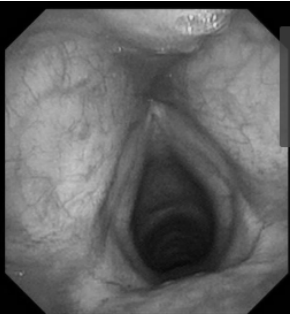

耳内镜检查:分泌性中耳炎(右)

电子喉镜检查:鼻息肉(双)

双耳鼓膜完整,右侧鼓膜内陷明显,右侧鼓室可见积液